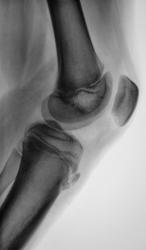

Пациент направлен врачом хирургом для рентгенографии коленного сустава с диагнозом - "Болезнь Осгут-Шлаттера?". Произведено стандартное исследование.

Да это остеохондропатия бугристости больше берцовой кости(неоднородная дефрагментация), желательно бы ещё аналогичный суставчик снять.

А вот так данная патология выглядит на МРТ: